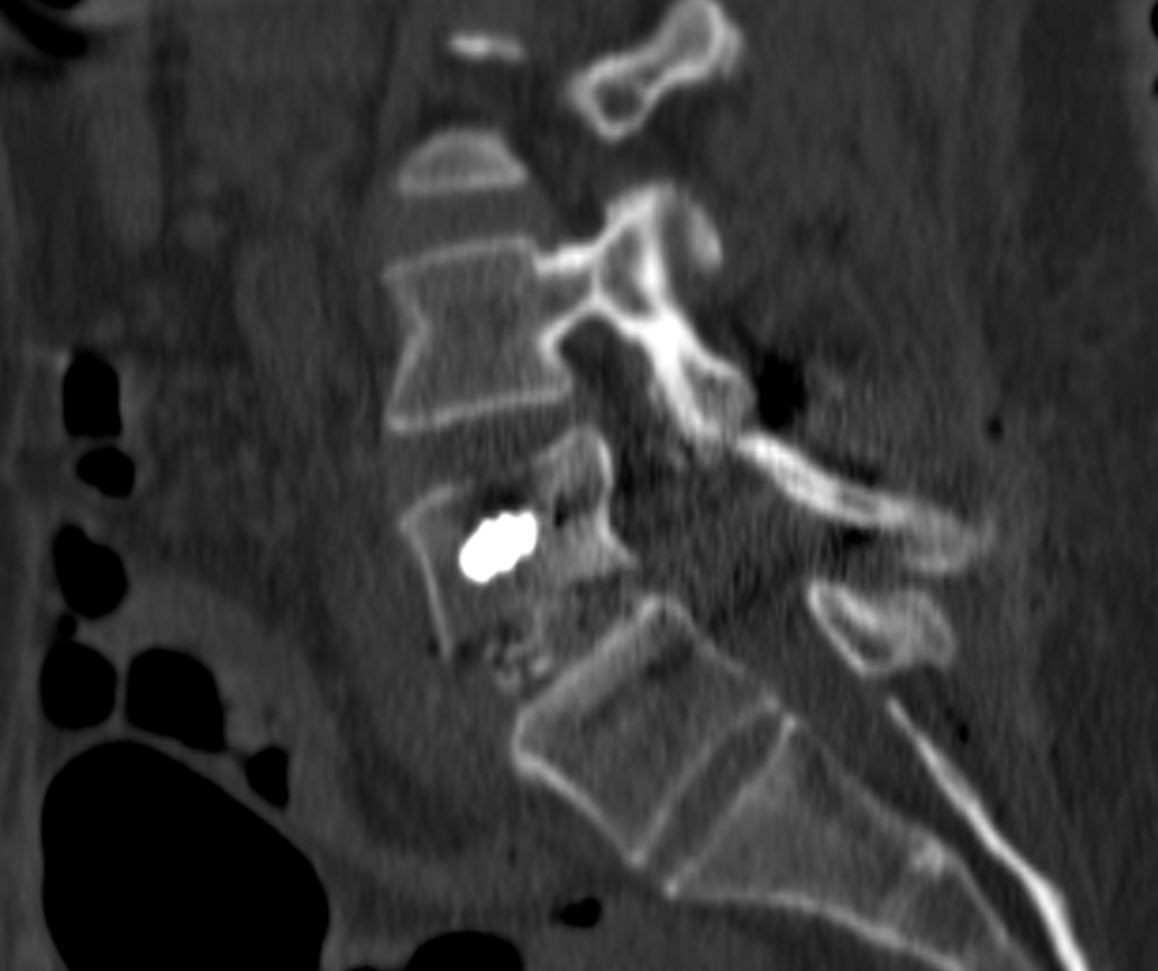

Διενεργήθη διαδερμική (ελάχιστα επεμβατική) σπονδυλοδεσία στο επίπεδο Ο4/Ο5

Η διαδερμική σπονδυλοδεσία μπορεί να χρησιμοποιηθεί ακόμα και οταν υπάρχει σπονδυλολίσθηση, αρκεί να μην είναι μεγάλου βαθμού. Σημαντικό είναι να τοποθετηθεί αρκετό οστικό μόσχευμα (πχ. στο μεσοσπονδύλιο διάστημα) προκειμένω να επιτευχθεί η «συνένωση» των σπονδύλων. Έτσι, επιτυγχάνεται ανάταξη της ολίσθησης και αποκατάσταση της σωστής ανατομίας της σπονδυλικής στήλης αλλά και ο ασθενής επωφελείται απο τα πλεονεκτήματα των ελάχιστα επεμβατικών τεχνικών.